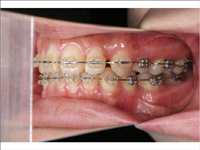

矯正の症例

| 【Before】 | 【After】 | |